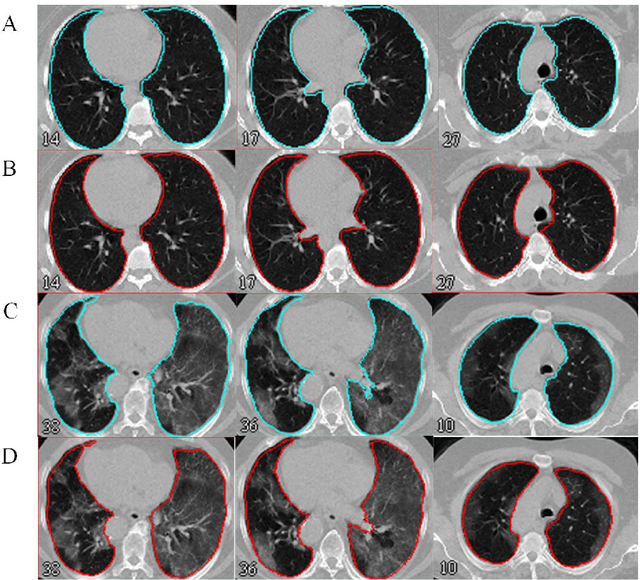

Abstract:Automated semantic image segmentation is an essential step in quantitative image analysis and disease diagnosis. This study investigates the performance of a deep learning-based model for lung segmentation from CT images for normal and COVID-19 patients. Chest CT images and corresponding lung masks of 1200 confirmed COVID-19 cases were used for training a residual neural network. The reference lung masks were generated through semi-automated/manual segmentation of the CT images. The performance of the model was evaluated on two distinct external test datasets including 120 normal and COVID-19 subjects, and the results of these groups were compared to each other. Different evaluation metrics such as dice coefficient (DSC), mean absolute error (MAE), relative mean HU difference, and relative volume difference were calculated to assess the accuracy of the predicted lung masks. The proposed deep learning method achieved DSC of 0.980 and 0.971 for normal and COVID-19 subjects, respectively, demonstrating significant overlap between predicted and reference lung masks. Moreover, MAEs of 0.037 HU and 0.061 HU, relative mean HU difference of -2.679% and -4.403%, and relative volume difference of 2.405% and 5.928% were obtained for normal and COVID-19 subjects, respectively. The comparable performance in lung segmentation of the normal and COVID-19 patients indicates the accuracy of the model for the identification of the lung tissue in the presence of the COVID-19 induced infections (though slightly better performance was observed for normal patients). The promising results achieved by the proposed deep learning-based model demonstrated its reliability in COVID-19 lung segmentation. This prerequisite step would lead to a more efficient and robust pneumonia lesion analysis.